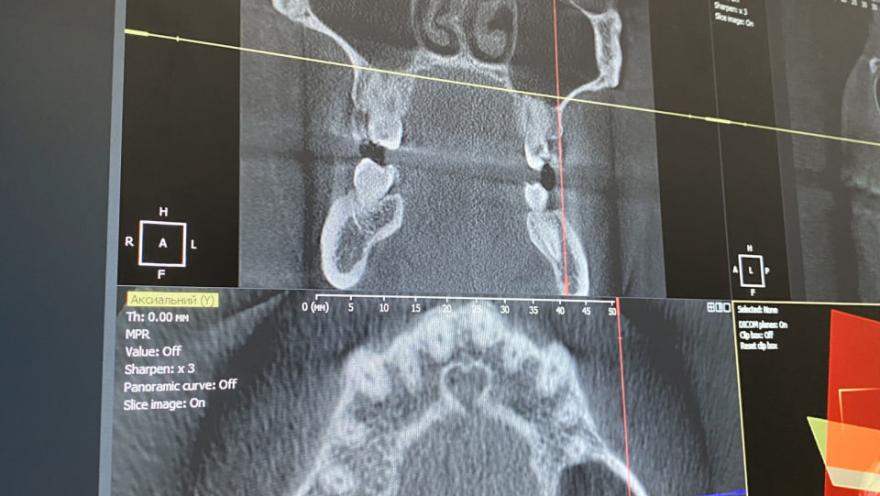

Спектр услуг клиники охватывает все направления современной стоматологии, с акцентом на сохранение естественности и функциональности. Врачи мастерски проводят терапевтическое лечение и эндодонтию под микроскопом, что гарантирует ювелирную точность в сохранении собственных зубов пациента. Особое направление — эстетическая трансформация: создание безупречных керамических виниров и художественных реставраций, которые выглядят настолько натурально, что их невозможно отличить от настоящей эмали. Для полного восстановления улыбки в Dental Story предлагают надёжную имплантацию и протезирование с использованием современных цифровых протоколов.